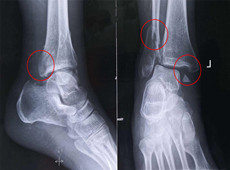

【醫療科普】踝關節骨折的主要類型及其影像學表現

大家好,我是南京醫科大學第二附屬醫院骨科副主任醫師王伯堯,從事骨科臨床工作十余年,擁有豐富的骨科臨床經驗,主要研究方向為骨科手術機器人的開發與臨床應用,今天跟大家介紹踝關節骨折的幾種常見類型及其在X影像上的表現。接下來跟...